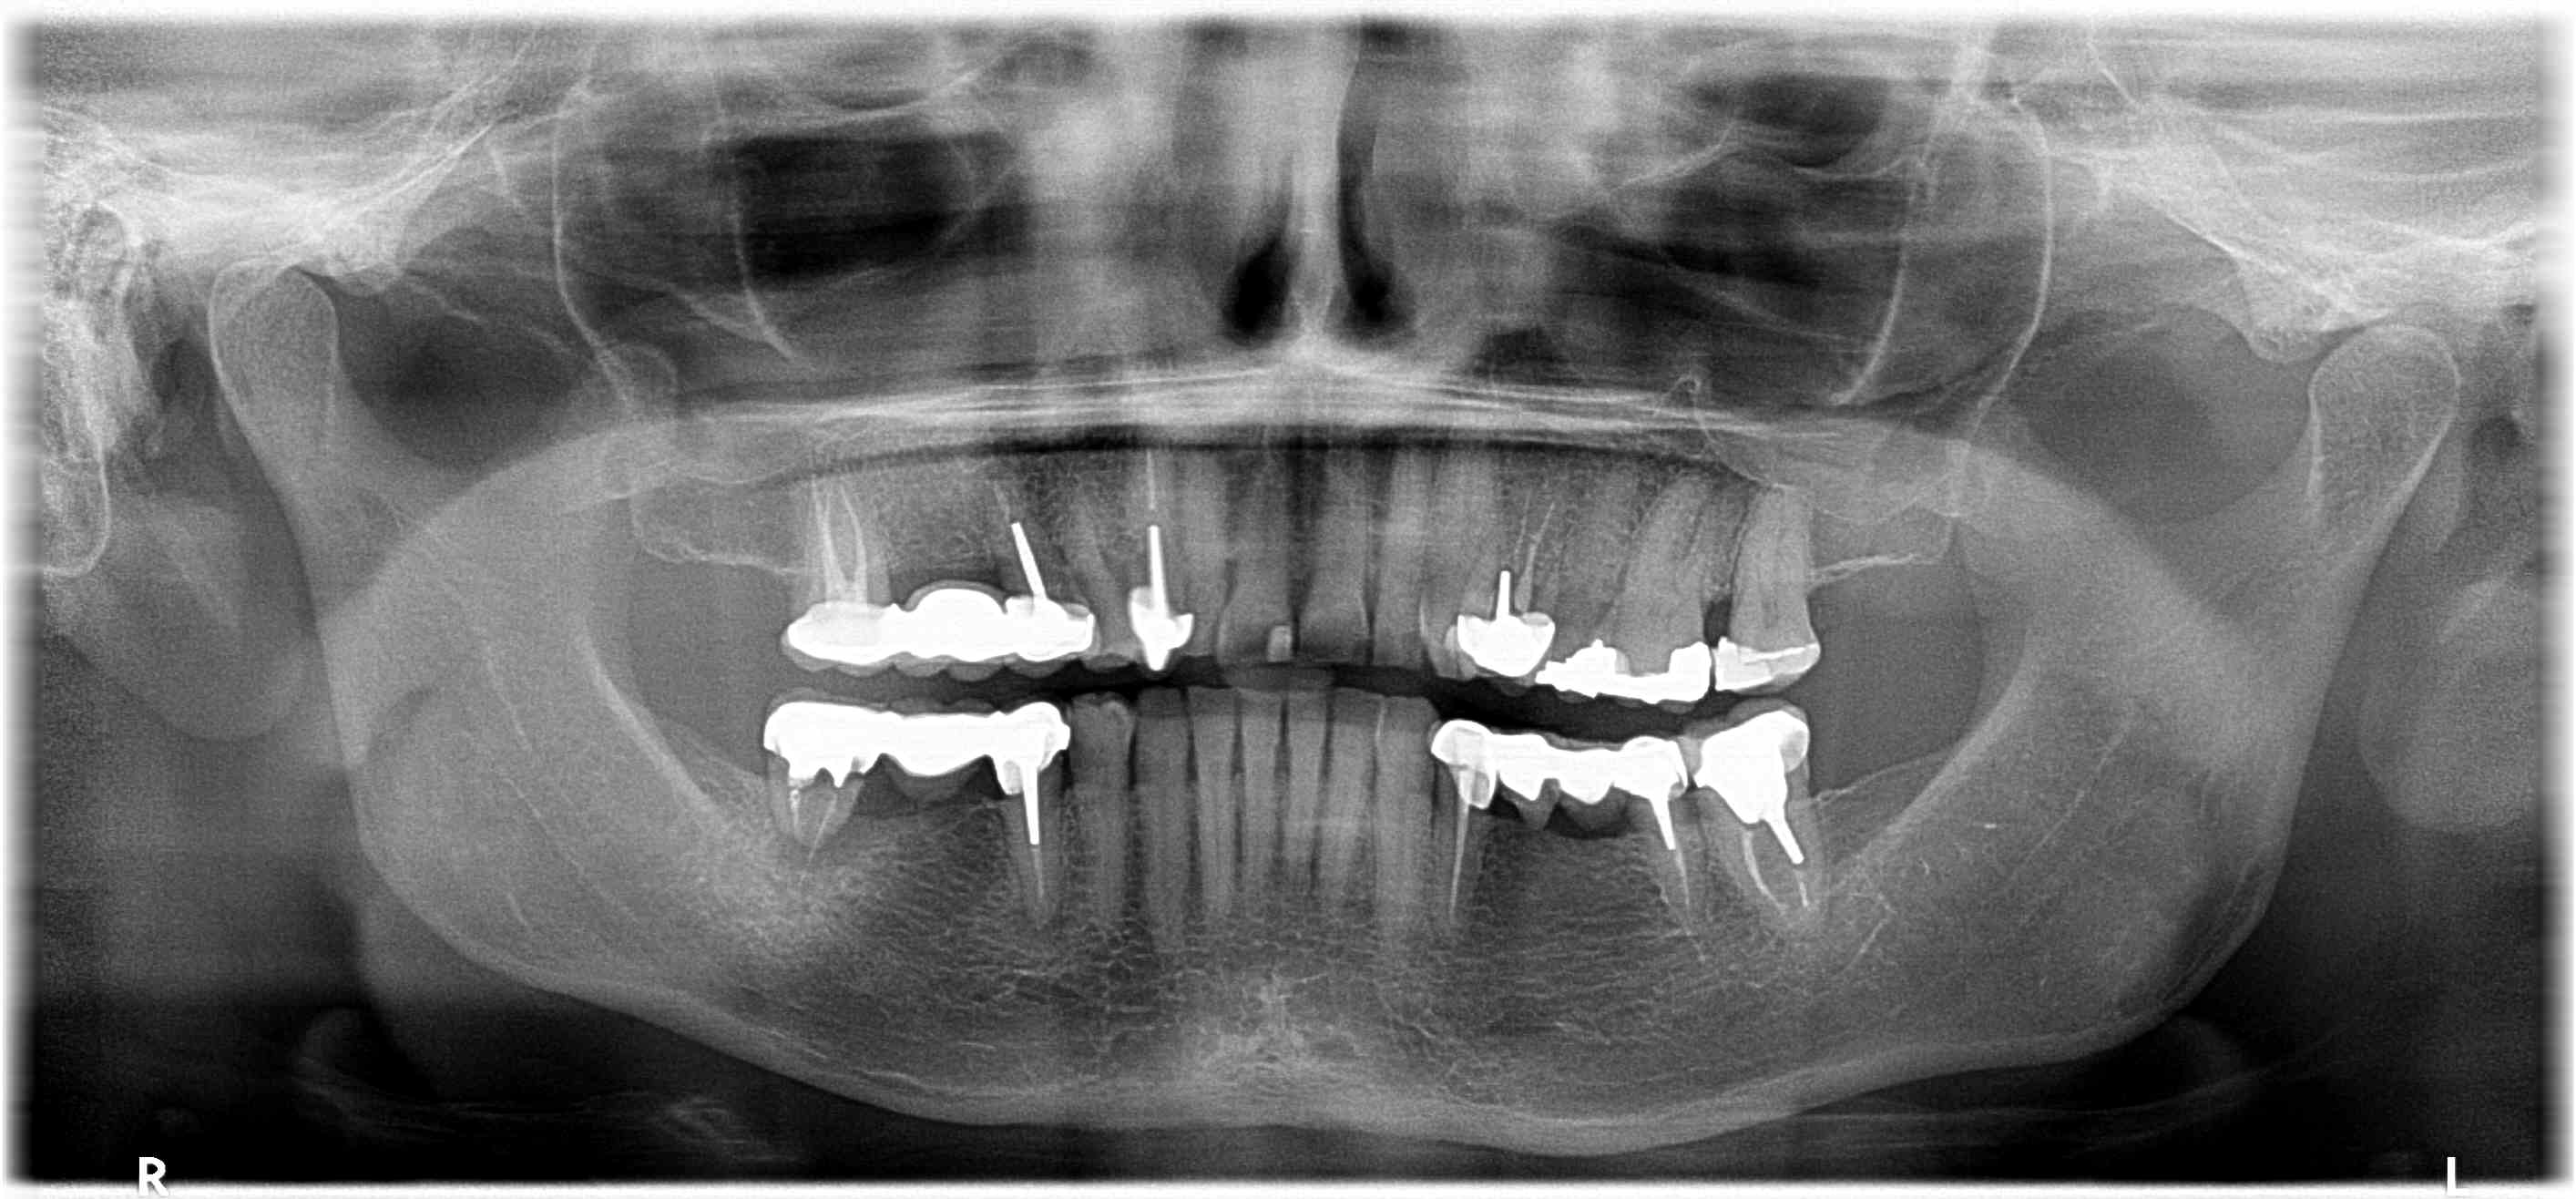

Ce viaduc, j'ai du le faire en 2008. depuis j'ai implanté secteur 4 et anterieur sup, mais il était toujours là en 2019...

Si ça peut te servir...